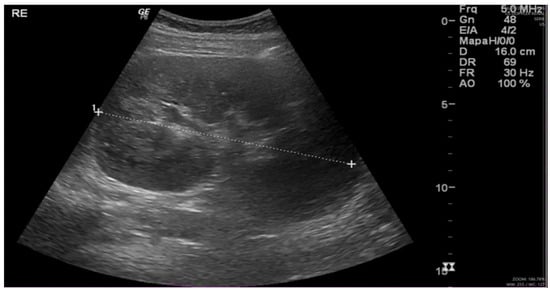

| Ultrasound (kidney size, in cm)  | RK = 12.4 LK = 13.3 | RK = 15.8 LK = 16 (day 25) + kidney biopsy (day 27)  | |||||